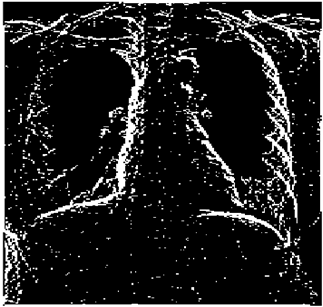

Table 11. Edge-detected image of “X-ray 2” after binarization for different noises.

NoiseCannyStandardSmooth

No noise Mathematics 10 02421 i093 Mathematics 10 02421 i094 Mathematics 10 02421 i095

G(0.001) Mathematics 10 02421 i096 Mathematics 10 02421 i097 Mathematics 10 02421 i098

G(0.002) Mathematics 10 02421 i099 Mathematics 10 02421 i100 Mathematics 10 02421 i101

G(0.003) Mathematics 10 02421 i102 Mathematics 10 02421 i103 Mathematics 10 02421 i104

I(0.25%) Mathematics 10 02421 i105 Mathematics 10 02421 i106 Mathematics 10 02421 i107

I(0.5%) Mathematics 10 02421 i108 Mathematics 10 02421 i109 Mathematics 10 02421 i110

I(1%) Mathematics 10 02421 i111 Mathematics 10 02421 i112 Mathematics 10 02421 i113

For Table 11, Table 12 and Table 13, the same points of Table 10 can be made. Therefore, for the sake of brevity, the points are not mentioned.